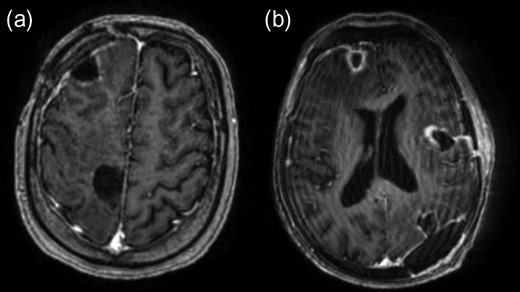

A CT brain revealed a right frontal mass lesion with surrounding oedema which was concerning for malignancy when taken in conjunction with the weight loss. Investigations for a primary tumour were negative including a CT of the chest, abdomen and pelvis in addition to upper GI endoscopy. Tumour markers did not reveal any abnormality. Additional testing for immunocompromise including HIV was negative and no primary source of infection was identified. A subsequent MRI brain revealed a total of five ring-enhancing lesions with vasogenic oedema distributed throughout both cerebral hemispheres with the largest measuring >2 cm (Fig. 1).

Initial post-contrast T1-weighted MRI demonstrating three lesions involving the right frontal lobe (a, b, c) with another in the left lateral occipital lobe (d) and one in the left insular region (d). The lesions also displayed complex walls typical of an abscess capsule on T2-weighted imaging and demonstrated central diffusion restriction (not shown).